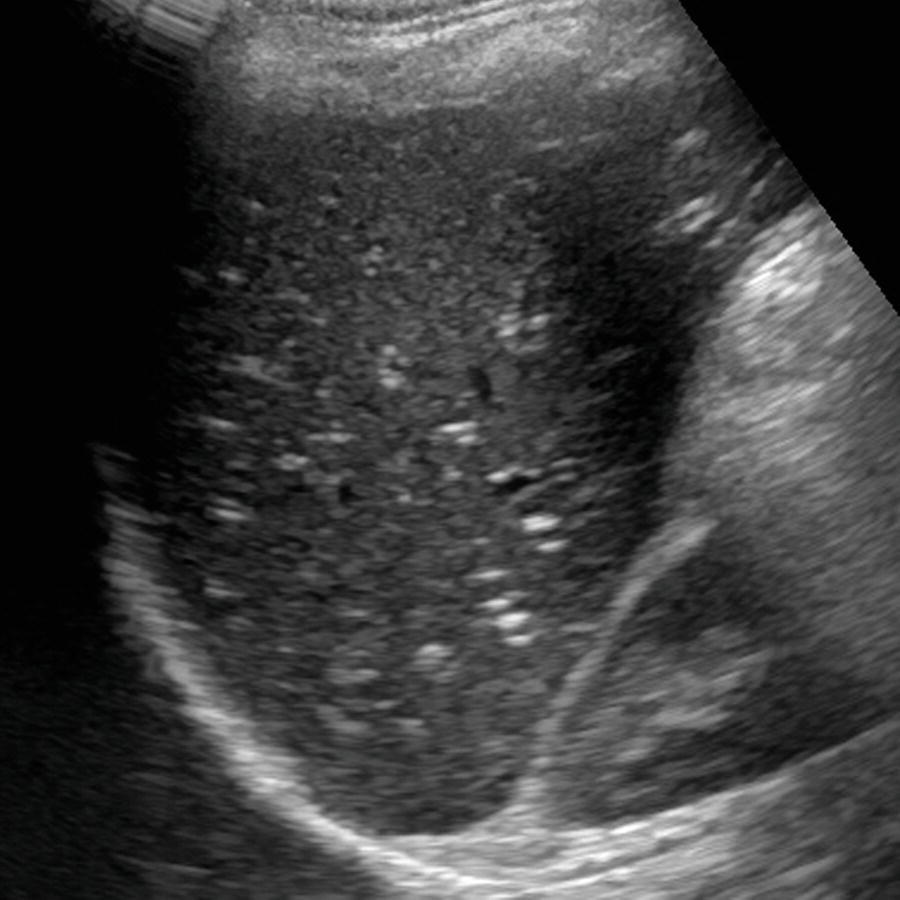

Fatty Liver In Ultrasound – Herbs and Food Recipes

Diffuse fatty liver | Radiology Case | Radiopaedia.org

Qualitative assessment of liver fat with conventional ultrasound. (A …

Fatty Liver Disease – Ultrasound | RADIOLOGYPICS.COM

Practice of Ultrasound: Part 13 — Liver fat and fibrosis